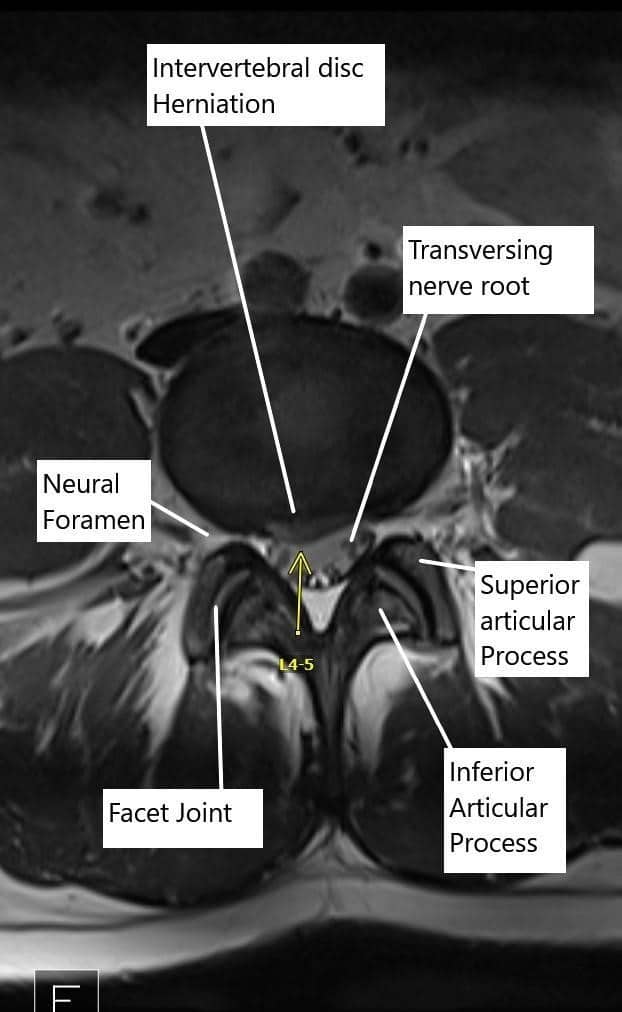

Examinó a pacientes de 18 años o más que presentaban dolor irradiado por debajo de la rodilla y/o debilidad muscular, y fueron diagnosticados con hernia discal lumbar según escáneres de imagen.

El dolor lumbar (LBP) se refiere a molestias o dolor localizado en la zona lumbar, mientras que la ciática implica un dolor que se irradia a lo largo del nervio ciático, que va desde la parte baja de la espalda hacia abajo en la pierna. La ciática suele ser causada por una compresión o irritación nerviosa, a menudo debido a una hernia discal.

La ciática suele ser causada por una hernia o un disco abultado en la parte baja de la columna, que comprime el nervio ciático. Otras causas incluyen estenosis espinal, enfermedad degenerativa del disco y, a veces, tumores o traumatismos en la columna.